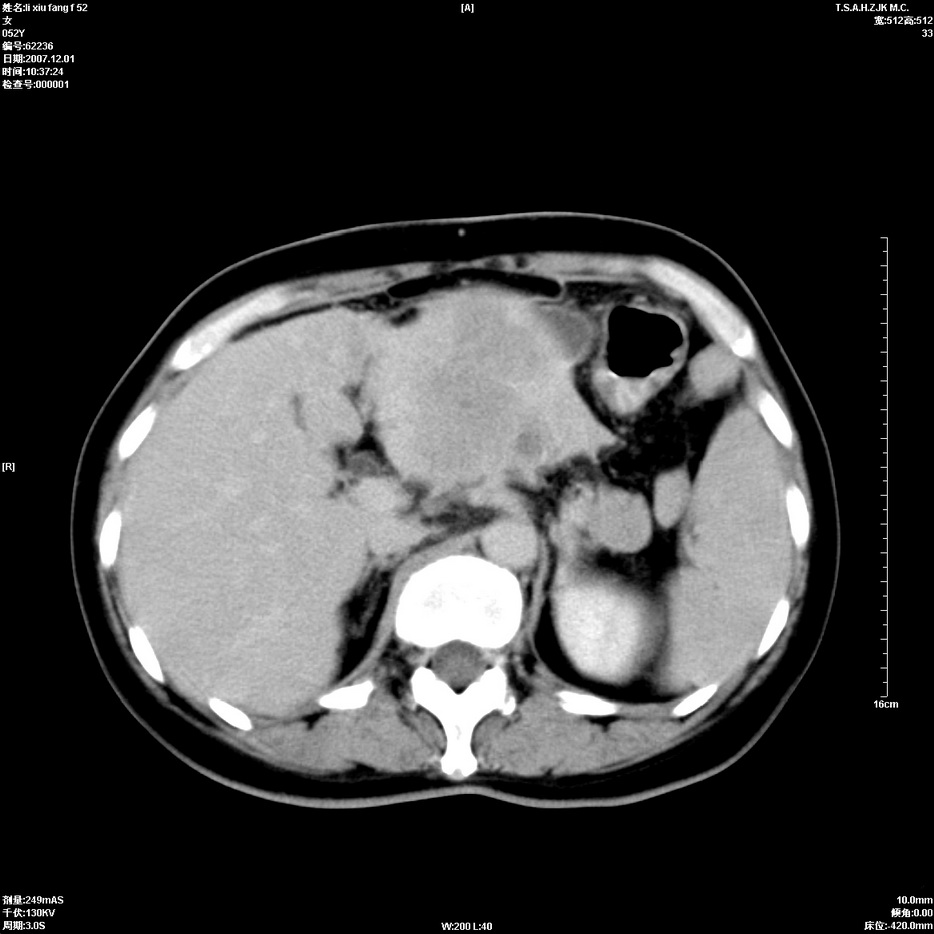

标题: CT12858:女,52岁,胎甲球蛋白861肝左叶占位,肝癌。下腔静 [打印本页]

标题: CT12858:女,52岁,胎甲球蛋白861肝左叶占位,肝癌。下腔静

肝左叶巨大低密度灶肿块,增强符合快进快出表现,有动静脉交通支;静脉期,下腔静脉内有充盈缺损,afp明显升高,支持肝癌并下腔静脉癌栓形成。

支持楼主   门静脉主干及左支癌栓形成

以下是引用拾荒者在2008-4-15 22:57:00的发言:[br]肝左叶巨大低密度灶肿块,增强符合快进快出表现,有动静脉交通支;静脉期,下腔静脉内有充盈缺损,afp明显升高,支持肝癌并下腔静脉癌栓形成。